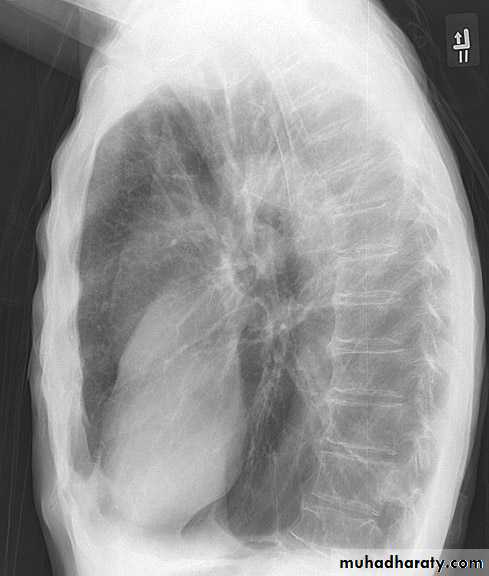

2- lateral.

Lateral view position